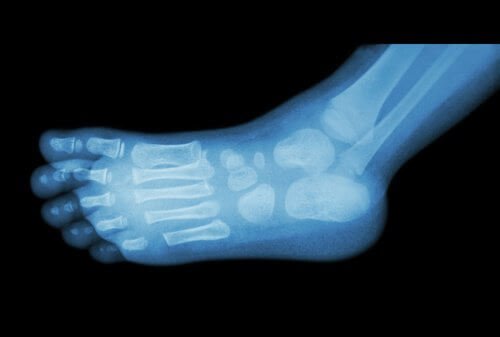

Pour le diagnostiquer, les médecins utilisent les méthodes classiques de radiologie. Cependant, l’épine peut également être visible à l’œil nu car elle provoque de petites protubérances, formées par l’accumulation de calcium.